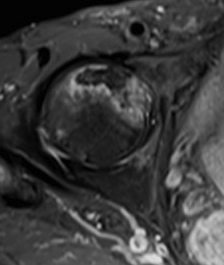

MRI

T1

T2

T2 Double Line Sign

Two lines virtually diagnostic of AVN

- outer line / low signa intensity

- inner line / high signal intensity / hypervascular granulation tissue

Modified Kerboul Combined Necrotic Angle (CNA)

Adding the arc of the femoral head necrosis

- mid-sagittal and mid-coronal MRI

- low risk collapse: < 190 degrees

- moderate risk collapse: 190 - 240 degrees

- high risk collapse: > 240 degrees